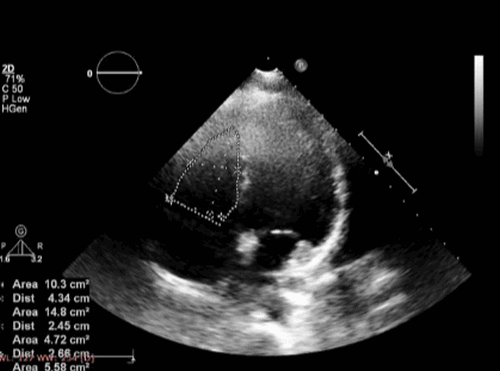

Эхокардиография обнаруживает следующие характерные признаки гипоплазии сердца: стеноз устья аорты и ее восходящего отдела, уменьшение размеров левого желудочка и увеличение правого желудочка, грубые изменения митрального клапана.

Характерным электрокардиографическим поиском у пациентов с АДПЖ - это нахождение эпсилон-волны или локализованного удлинения комплекса QRS в правых грудных отведениях (в V1 -V3). Клинические признаки недостаточности правого желудочка и дисфункции левого желудочка, а также желудочковой тахикардии являются плохими прогностическими факторами. Трудно диагностировать АДПЖ без визуализации сердца, то есть без проведения эхокардиографии. Исследования правого желудочка в группе дисплазий показало, что эхокардиографические находки были у большинства пациентов с АДПЖ. Величина систолического и диастолического диаметров выводного тракта и притока были увеличены, причем было увеличение диастолического размера выводного тракта ПЖ (ВТПЖ), которые наиболее распространены.

Диаметр ВТПЖ был более 25 мм у всех пациентов. Если размер ВТПЖ больше, чем 30 мм по парастернальной длинной оси, то признак располагал значительной чувствительностью (90%) и специфичностью (88%) для диагностики АДПЖ. Функция ПЖ был ненормальный у 70% пациентов. Кроме того, региональные аномалии движения миокарда ПЖ на эхокардиографии были частыми, и наиболее значимыми в области верхушки и передней стенки. Морфологические нарушения ПЖ заключались в резко трабекулярной структуре внутренней выстилки, утолщении модераторного пучка, и присутствовии мешкообразных изменений в передней стенке ПЖ у 54%, 34% и 17% пациентов соответственно.

- УЗИ сердца. На ЭхоКГ определяется конечный диастолический размер (КДР) и конечный систолический размер (КСР) желудочков, после чего эти данные сравниваются между собой. Если отношение КДР правого желудочка к КДР левого составляет 0,5 и более, это свидетельствует в пользу наличия АП КМП.